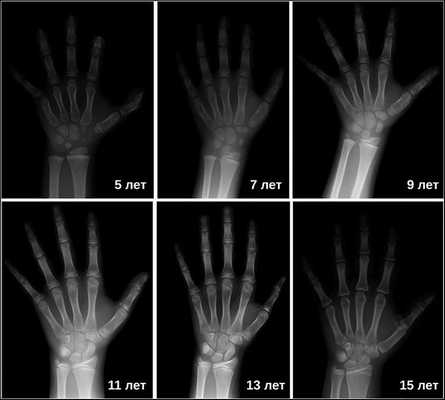

Для выявления опухолей гипофиза проводится рентгенография черепа, КТ и МРТ головного мозга. При наличии аденомы гипофиза определяется увеличенное турецкое седло (ложе гипофиза). Рентгенограммы кистей рук показывают несоответствие между костным и паспортным возрастом. При офтальмологическом обследовании пациентов с гигантизмом выявляется ограничение зрительных полей, застойные явления в глазном дне.

Затем врачи определяют костный возраст. Сделать это можно с помощью рентгена или УЗИ запястья. В норме костный возраст может отставать или опережать паспортный на два года.